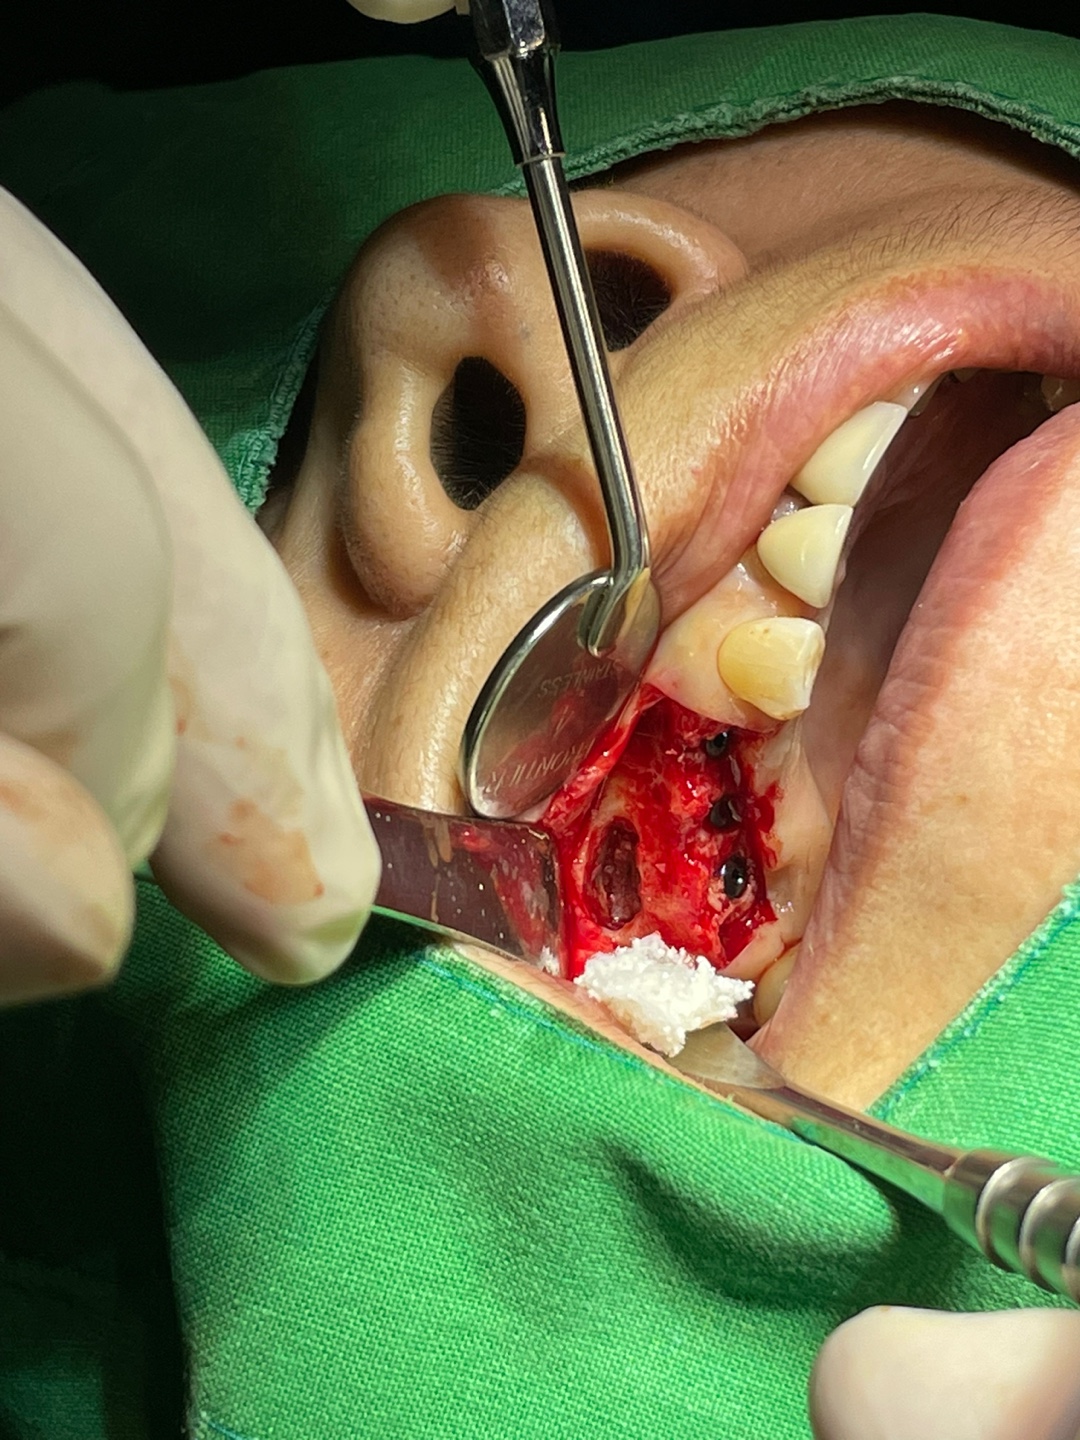

각과정별로 상악동 거상술이 어떤 것인지 쉽게 알 수 있을 것입니다.

이번 포스팅에서는 사진을 보면 막연하던 상악동거상술이 어떻게 진행되었는지를 알 수 있습니다.

그냥 코옆 공기 주머니에다가 이식한다고 하면 환자분이 막연하게 생각하실수 있겠지만

위의 사진을 본다면 구체적으로 어떤 방법으로 진행되는지 감을 잡을 수 있을 겁니다.

저는 상악동 거상술을 몇천회 이상 시행했지만

항상 저 막이 찢어지지 않게 최대한 조심합니다.